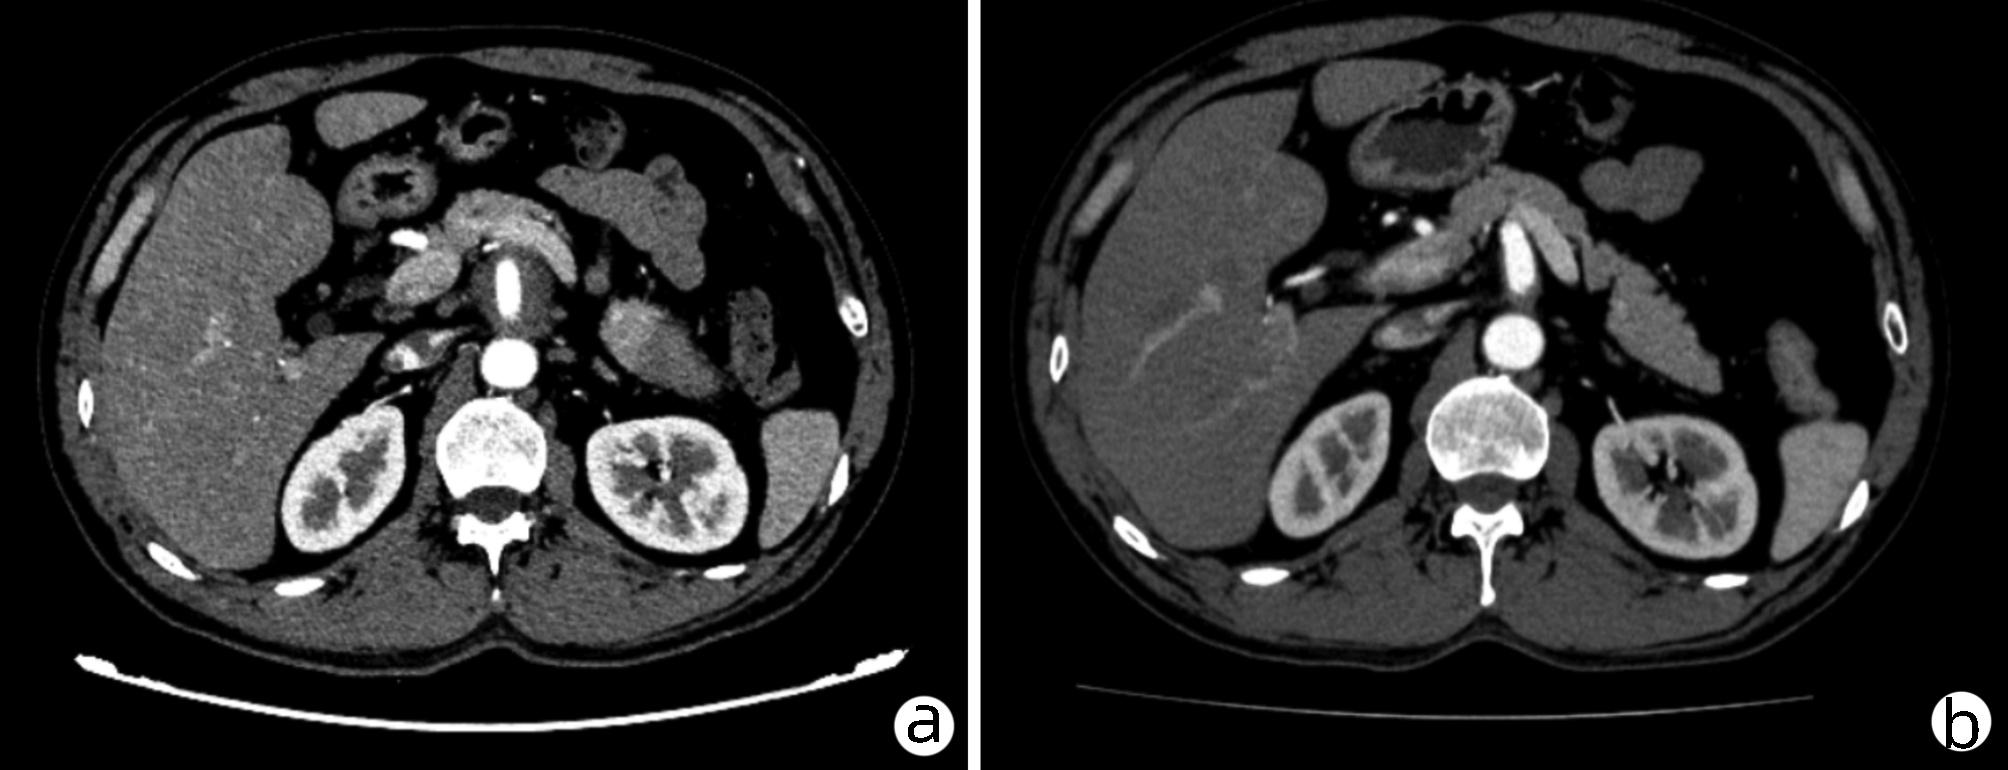

乙型肝炎肝硬化上消化道出血的ΔCT特征性表现及预测模型的建立

李俊杰, 孙岩岩, 李将宏, 郑虹

2022, 38(5): 1081-1085. DOI: 10.3969/j.issn.1001-5256.2022.05.020

摘要(1053) HTML (308) PDF (2671KB)(64)

摘要:

目的  本研究旨在寻找乙型肝炎肝硬化CT特征,建立肝硬化上消化道出血预测模型,预测出血风险。  方法  回顾性分析2015年1月—2021年6月天津市第一中心医院101例型肝炎肝硬化患者的数据,将其分为上消化道出血组(P=58)及非出血组(n=43)。比较两组间实验室检查以及强化CT检查测的平扫期、动脉期、门脉期以及静脉期的CT值,并计算各期间CT值的变化(ΔCT)。计量资料两组间的比较使用t检验或Mann-Whitney U检验;使用logistic回归分析方法,预测相关危险因素;通过计算受试者工作特征曲线下的面积评估模型辨别力,而模型校准则通过Hosmer-Lemeshow确定。在多变量logistic回归分析结果的基础上,使用Rstudio4.1.2软件的R包构建预测的列线图模型,并绘制相应的ROC曲线、校准曲线以及临床决策曲线。  结果  非出血组血清TBil、WBC、PLT水平与出血组比较,差异均有统计学意义(P值均<0.05);两组在肝-Plain、脾-P-Plain、脾-P-A ΔCT值存在统计学差异(P值均<0.05)。单因素logistic分析结果显示,白细胞(OR=0.770,95%CI:0.624~0952, P=0.016)、血小板(OR=0.979,95%CI:0.965~0.994, P=0.006)、肝脏平扫期(OR=1.142,95%CI:1.058~1.233, P=0.001)、脾脏门脉期-平扫ΔCT值(OR=0.979,95%CI:0.959~1.000, P=0.050)、脾脏门脉期-动脉期ΔCT值(OR=0.979,95%CI:0.944~0.994, P=0.015)在乙型肝炎肝硬化患者发生上消化道出血与未出血两者之间差异具有统计学意义。多因素logistic分析结果显示血小板(OR=0.968,95%CI:0.944~0.993, P=0.011)、肝脏平扫期(OR=1.148,95%CI:1.047~1.259, P=0.003)、脾脏门脉期-动脉期ΔCT值(OR=0.951,95%CI:0.908~0.995, P=0.030)为上消化道出血的独立危险因素。基于多因素logistic分析结果,构建了乙型肝炎肝硬化上消化道出血的预测模型并绘制校准曲线。该模型的受试者特征曲线下面积为0.801,cut-off值为0.433,其对应的敏感度是81.4%,特异度是77.6%。模型的校准曲线与理想曲线贴合良好。  结论  乙型肝炎肝硬化肝脏具有特殊的ΔCT变化,通过ΔCT构建的预测模型对于乙型肝炎肝硬化上消化道出血具有良好的预测能力。